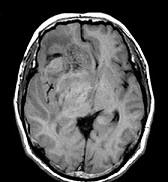

问题 男,55岁,头胀感1年余,头痛3日,请根据所提供图像,选择最可能的诊断()

选项 A.(右额颞)病毒性脑炎 B.(右额颞)星形细胞瘤 C.(右额颞)淋巴瘤 D.(右额颞)少突胶质细胞瘤 E.(右额颞)胶质母细胞瘤

答案 D